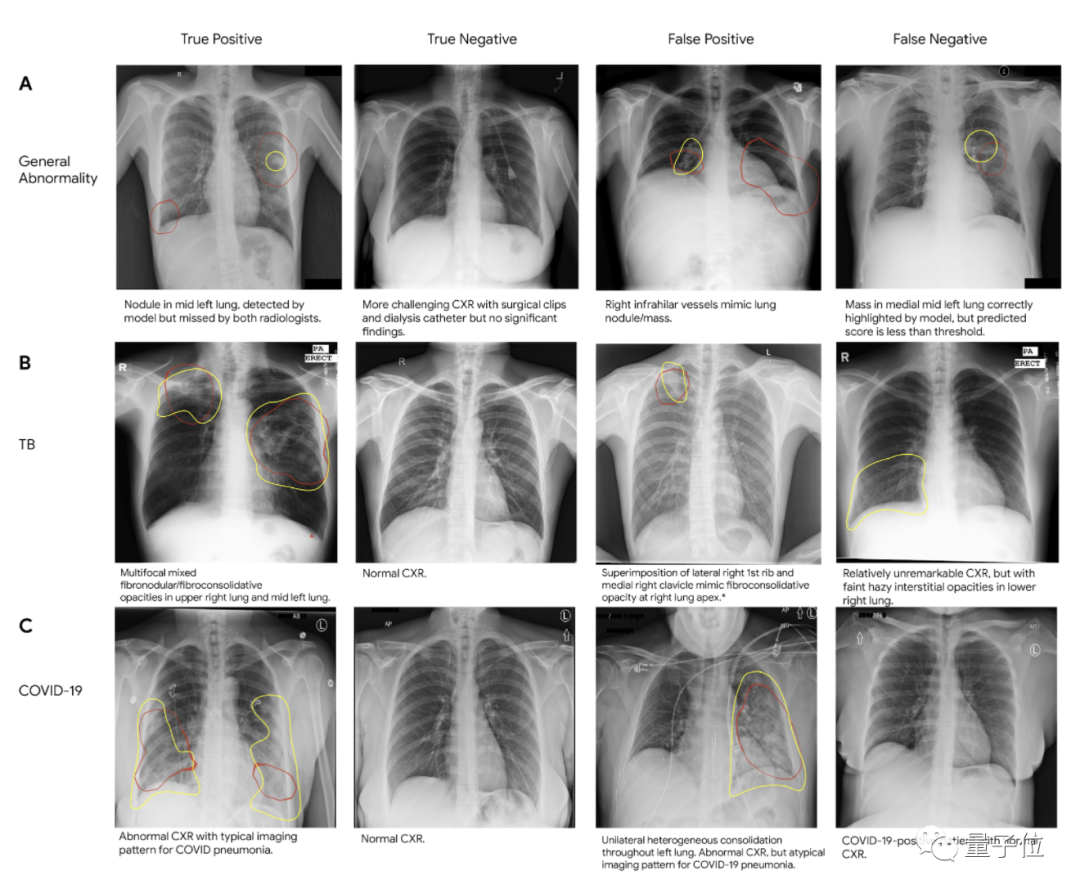

Jeff Dean还强调在疾病诊断,尤其是在医学成像上的应用,比如在改善乳腺癌筛检、检测肺癌、加速癌症的放射治疗、标记异常X射线和前列腺癌期活检等领域。